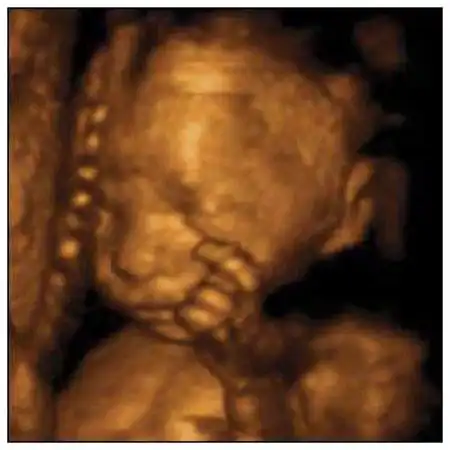

Создатель этой системы профессор Стюарт Кэмпбелл, один из ведущих акушеров Соединенного Королевства, стал знаменитостью в мире медицины благодаря снимкам, на которых зародыш улыбается (раньше считалось, что эта способность появляется лишь после рождения)...

Качество изображений превосходное!...

Специалисты признают, что эти снимки, прежде всего помогающие оценить правильность развития плода, завораживают...

12-я неделя. Оформились веки, мочки ушей, на пальчиках уже растут ноготки. Ребенок морщит губы, открывает и закрывает рот, может всасывать и глотать жидкость, которая его окружает.